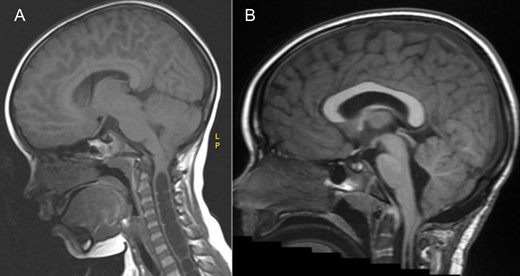

An MRI demonstrated a chiari one malformation (Fig. 1) with holocord syrinx (Fig. 2). No space occupying lesion was seen in the spine and the cord was not tethered. Neurophysiological investigations were carried out (Fig. 3), the child found the nerve conduction studies (NCS) and electromyography (EMG) difficult to tolerate however the findings were in keeping with pre-ganglionic pathology. There was evidence from the motor NCS and EMG of neurogenic abnormalities, including active denervation and re-innervation at the L4/5 level. These findings could have been at the level of the root or anterior horn. However, these findings were not considered typical for a peroneal neuropathy as the peroneal sensory potential was within normal limits.

MRI spine sagittal sections demonstrating a holocord syrinx decreasing in size following surgery. Pre (A) and 3 years post op (B) T2. Pre (C) and 3 years post op (D) and T1.

At 1 year follow-up, his foot drop had gradually improved. He was able to walk on his tip toes and heels. By 2 years follow-up, his foot drop had completely resolved and ankle dorsiflexion was 5/5 on the right. An MRI at three years post op demonstrated a good foramen magnum decompression (Fig. 1) and significant improvements in the syrinx (Fig. 2), however not complete resolution.